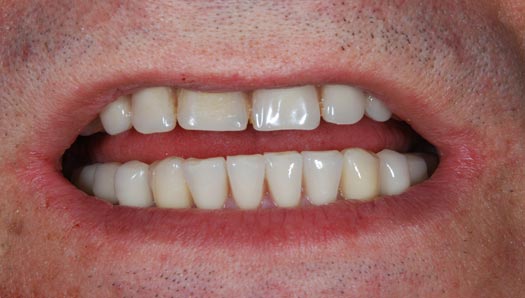

Riabilitazione gnatologica, ortodontica ed estetica

Durata del trattamento: un anno